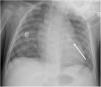

MethodsAll consecutive pediatric patients referred to our center for percutaneous PDA closure from January 2006 until September 2018 were included in this study. Medical record data was collected and reviewed retrospectively. Informed written consent was obtained from the parents or legal guardians. Indications for closure were presence of cardiac murmur, left-sided volume overload detected by non-invasive cardiac imaging, or signs of heart failure. All procedures were performed under general anesthesia. Arterial access was obtained in all patients. An intravenous bolus injection of 100 IU/kg heparin was administered at the start of the procedure. Our endocarditis prophylaxis protocol consisted of cephazolin 25-30 mg/kg every eight hours for 24 hours, and no anti-aggregation was advocated. In every patient, an aortogram was performed in the lateral projection to define the morphology and size of the duct. According to these results, feasibility for percutaneous closure was determined and, when deemed feasible, appropriate devices were selected. At our department, the Nit-Occlud® occlusion device (pfm, Cologne, Germany) has been available since 2006, with the Amplatzer™ duct occluder being implemented in 2011. As standard of care, all devices were preferably deployed anterogradely. A post-implantation aortogram was obtained to check for residual shunts or any anomaly in the device position. All patients were assessed six hours after the procedure for hemodynamic instability and unpalpable distal arterial pulses. The following day, before discharge, the location of the device was noted on a chest radiograph and a transthoracic echocardiography was performed to exclude residual leakage or other complications. Clinical and echocardiographic follow-up assessments were performed at one, three, six and twelve months after the procedure, and annually thereafter.

An early post-procedure complication rate of 1.8% was found (four patients). Three patients presented isolated loss of arterial pulse and were successfully treated with fibrinolytics. The most severe complication was in a seven month-old patient who presented device embolization 48 hours after the procedure. In this infant with a history of prematurity (born at 26 weeks of gestation), an Amplatzer duct occluder II Additional Sizes (5x6 mm) had been implanted. Loss of lower limb arterial pulse was noted a few hours after the procedure. A vascular doppler ultrasound confirmed occlusion of the femoral artery and thrombolysis with recombinant tissue plasminogen activator was started. After 48 hours, a chest radiograph revealed the device had migrated (Figure 13), with computed tomography confirming the device was at an inferior lobar branch of the left pulmonary artery. This required urgent surgical removal of the Amplatzer duct occluder II Additional Sizes and PDA ligation, which were both uneventful.